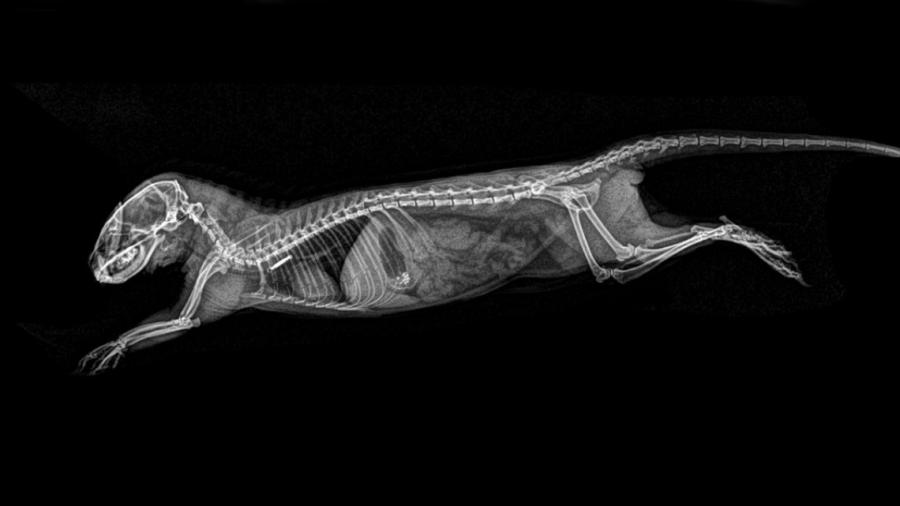

A pocos días de Halloween, el zoológico de Oregón, en Estados Unidos, decidió compartir hace unos días las imágenes hechas en rayos X de sus animales.

Las radiografías fueron hechas durante las inspecciones de salud rutinarias, por lo que en ninguna muestra a un animal enfermo o lastimado.